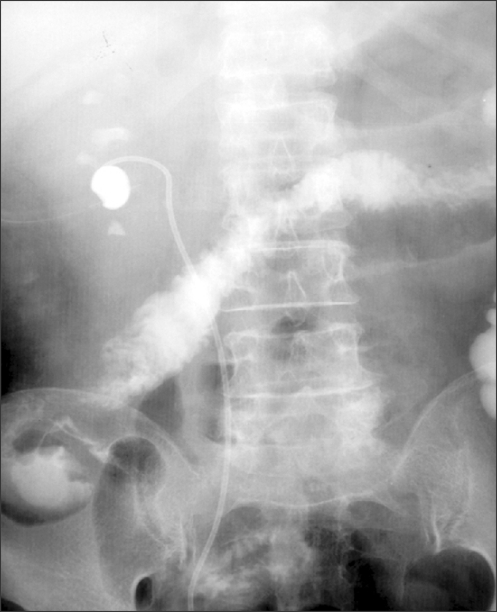

Ascending Colon Injury Of Percutaneous Nephrolithotomy | Open-i

colon injury percutaneous ascending nephrolithotomy figure transverse pnl descending performed contrast extravasated patient seen medium open